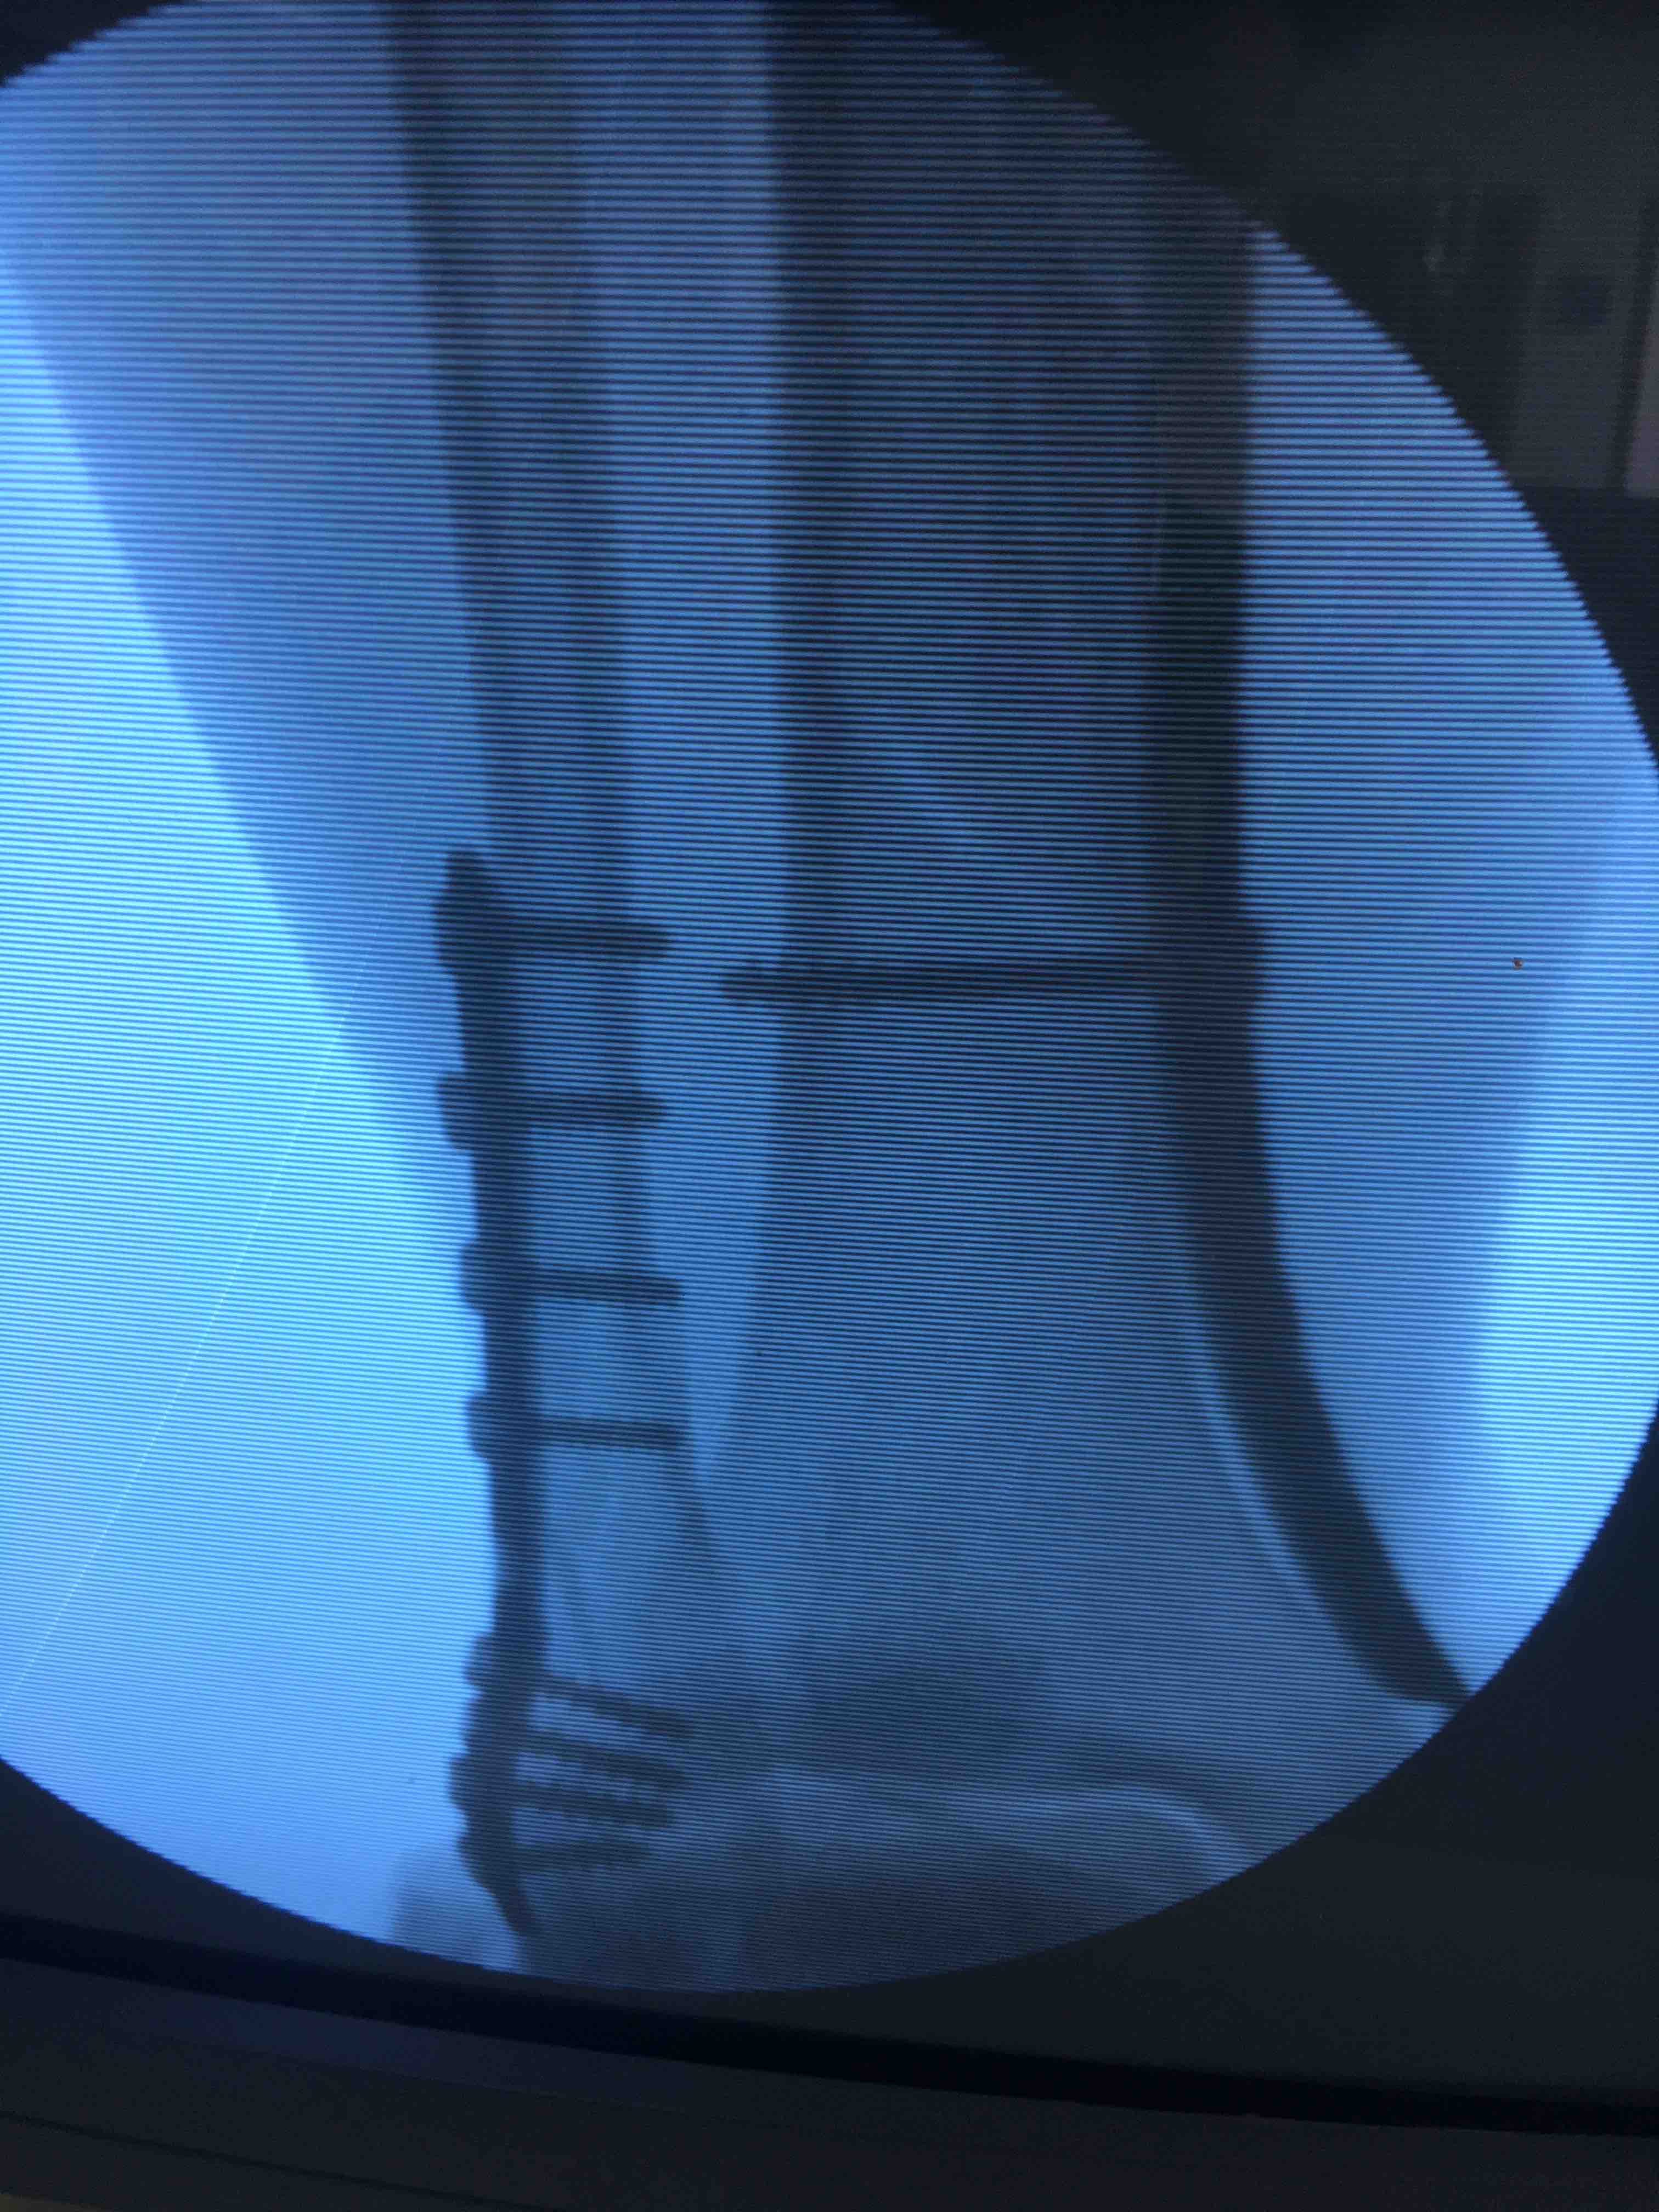

胫腓骨下段骨折(微创固定)

摔伤后右小腿肿痛,活动受限1小时入院。既往身体健康,无特殊不良嗜好。

生命体征平稳,心肺复未见明显异常。右小腿肿胀,局部皮色皮温正常,压痛及叩痛阳性,可及骨擦音,活动受限,末梢血运感觉正常。

在腰麻下行切复内固定术,术后抗炎,消肿对症治疗。